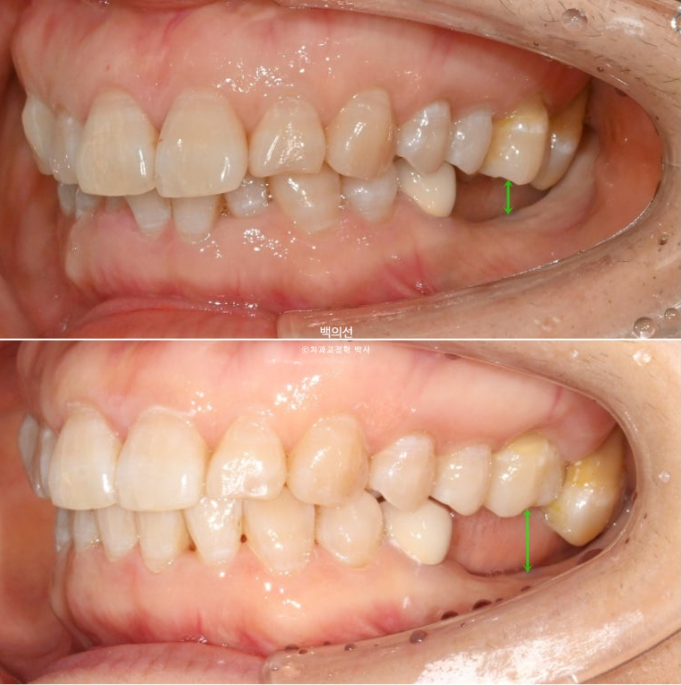

작년 9월, 앞니 돌출과 삐뚠치아 배열을 위해 오신 환자분입니다.

정면에서는 아래 앞니 일부가 윗니에 가려져 안 보일정도의 심한 과개교합을 보입니다.

좌측 아래는 어금니가 빠진 지 오래된 상태입니다.

앞니 두 개가 튀어나와 돌출이며

아래 앞니는 치아가 많이 겹쳐져 있습니다.

특히 가운데 앞니와 옆 앞니는 50% 정도가 겹쳐진 상태